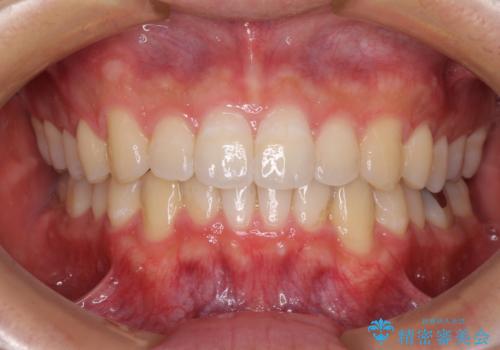

抜歯をして口元を下げなければならないほど出っ歯ではなかったため、少しずつ治療ゴールを変更しながら仕上げていきました。

気になっていた前歯の飛び出した印象は、最終的にはスッキリと引っ込み、大変満足していただきました。